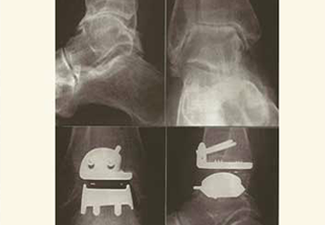

Prótesis

En la actualidad, y con un recorrido de más de 25 años de pruebas, existen en el mercado las prótesis para reemplazo total del tobillo, que si bien no son el tratamiento de elección primario, tienen sus indicaciones, obviamente contraindicaciones y complicaciones, como toda técnica quirúrgica.

Prótesis: